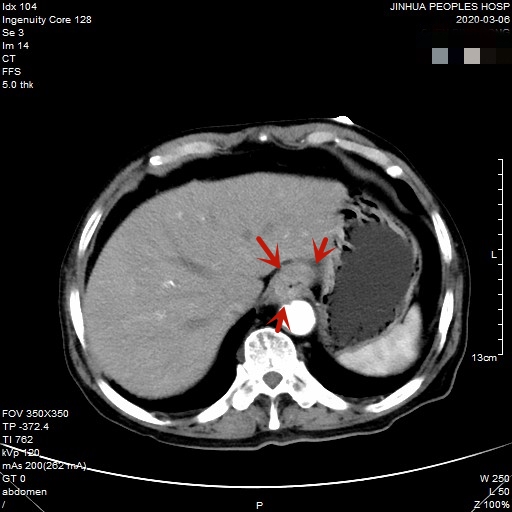

医生予以进一步检查CT增强发现肿瘤倒是没有明显侵犯周围脏器或结构,请我去会诊后,仔细阅片,发现从影像上看还是能够根治性切除的。所以转来胸外科拟进一步行手术治疗。下面是其CT增强的图像:

以上图片红色箭头所指处为贲门部肿瘤